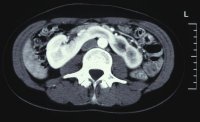

Im Ausscheidungsurogramm und im CT war eine Hufeisenniere mit Pyelektasie links zu erkennen (Abbildung 5).